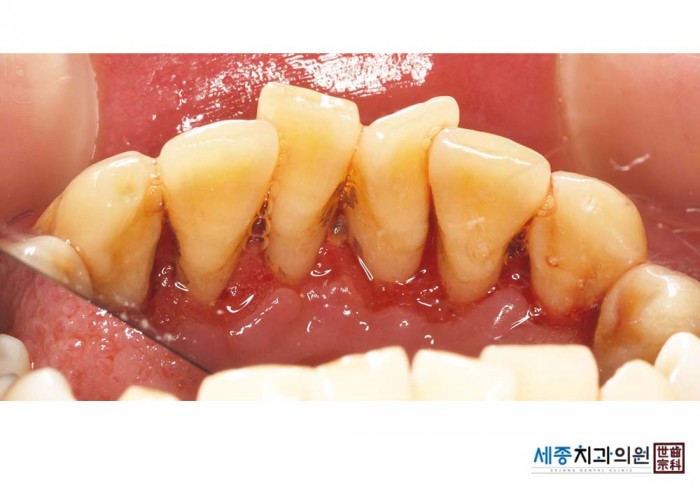

[스케일링] 치주질환 예방 스케일링

치료전 : 2025-02-10

가글마취&저주파 스켈러를 사용한 착색제거 스케일링